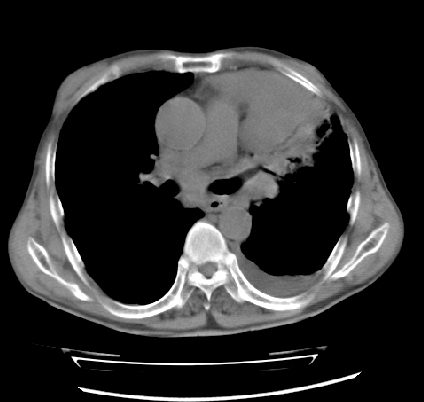

以下是引用ct诊断高手在2009-5-29 13:50:00的发言:[br]考虑左侧中央型肺癌,阻塞性肺炎伴肺不张。纵隔淋巴结转移。慢支 肺间质纤维化肺气肿。左侧胸腔积液。左侧肋骨转移?

以下是引用hhcckk在2009-5-29 14:58:00的发言:[br]左上周围型肺癌,左肺门、纵隔淋巴结转移,左侧胸腔积液,左侧肋骨转移[br]